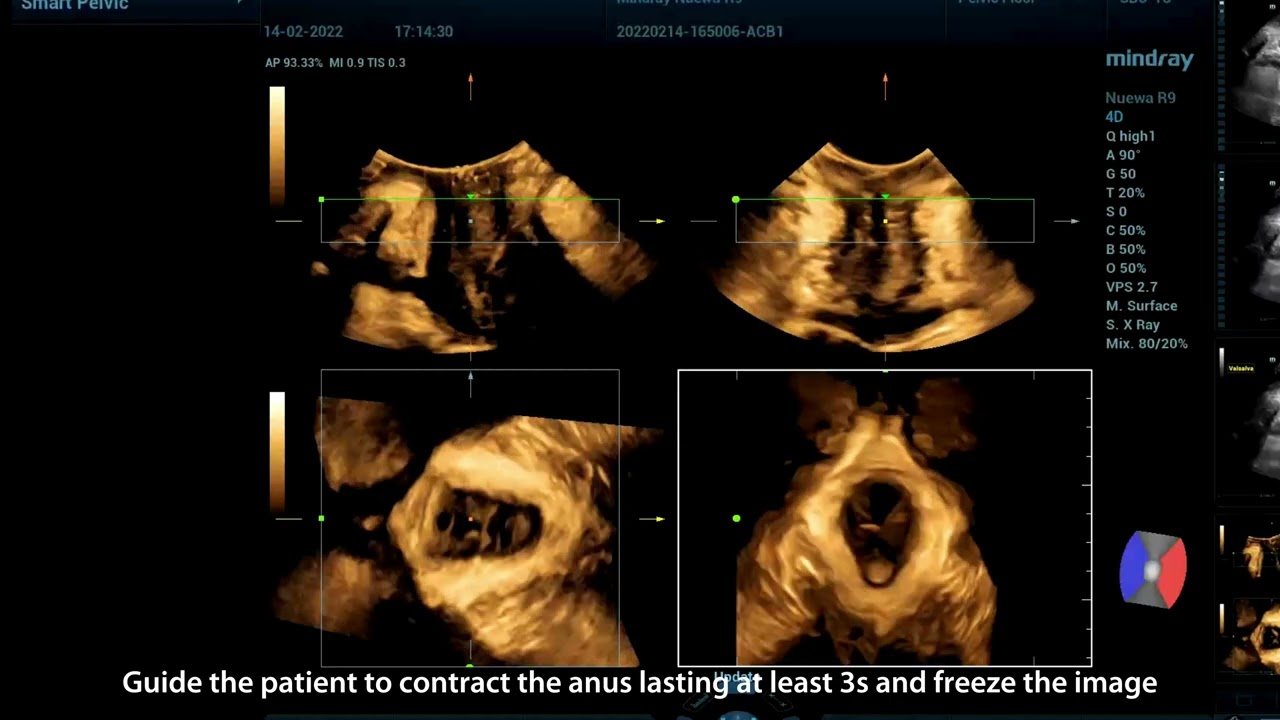

Mindray offers the most comprehensive portfolio of Point of Care ultrasound solutions that are easy to use, elevate your practice, and empower you to provide an even higher standard of care in a timely manner. From entry-level, touch-enabled systems to sophisticated, laptop or cart-based designs, our Point of Care ultrasound machines are an excellent choice to meet the demands of fast-paced environments such as Emergency Medicine, Critical Care, Anesthesia, and others.

MindrayŌĆÖs Point of Care ultrasound machines provide leading-edge technology and everyday applications that meet the diverse demands of your departments and the evolving needs of your patient population. Our innovative, accessible Point of Care ultrasound solutions offer sophisticated tools and technologies that empower you to streamline workflow, minimize the risk of infection, and provide the highest quality of care now and in the future. Experience peace of mind and see something better with Mindray Ultrasound.